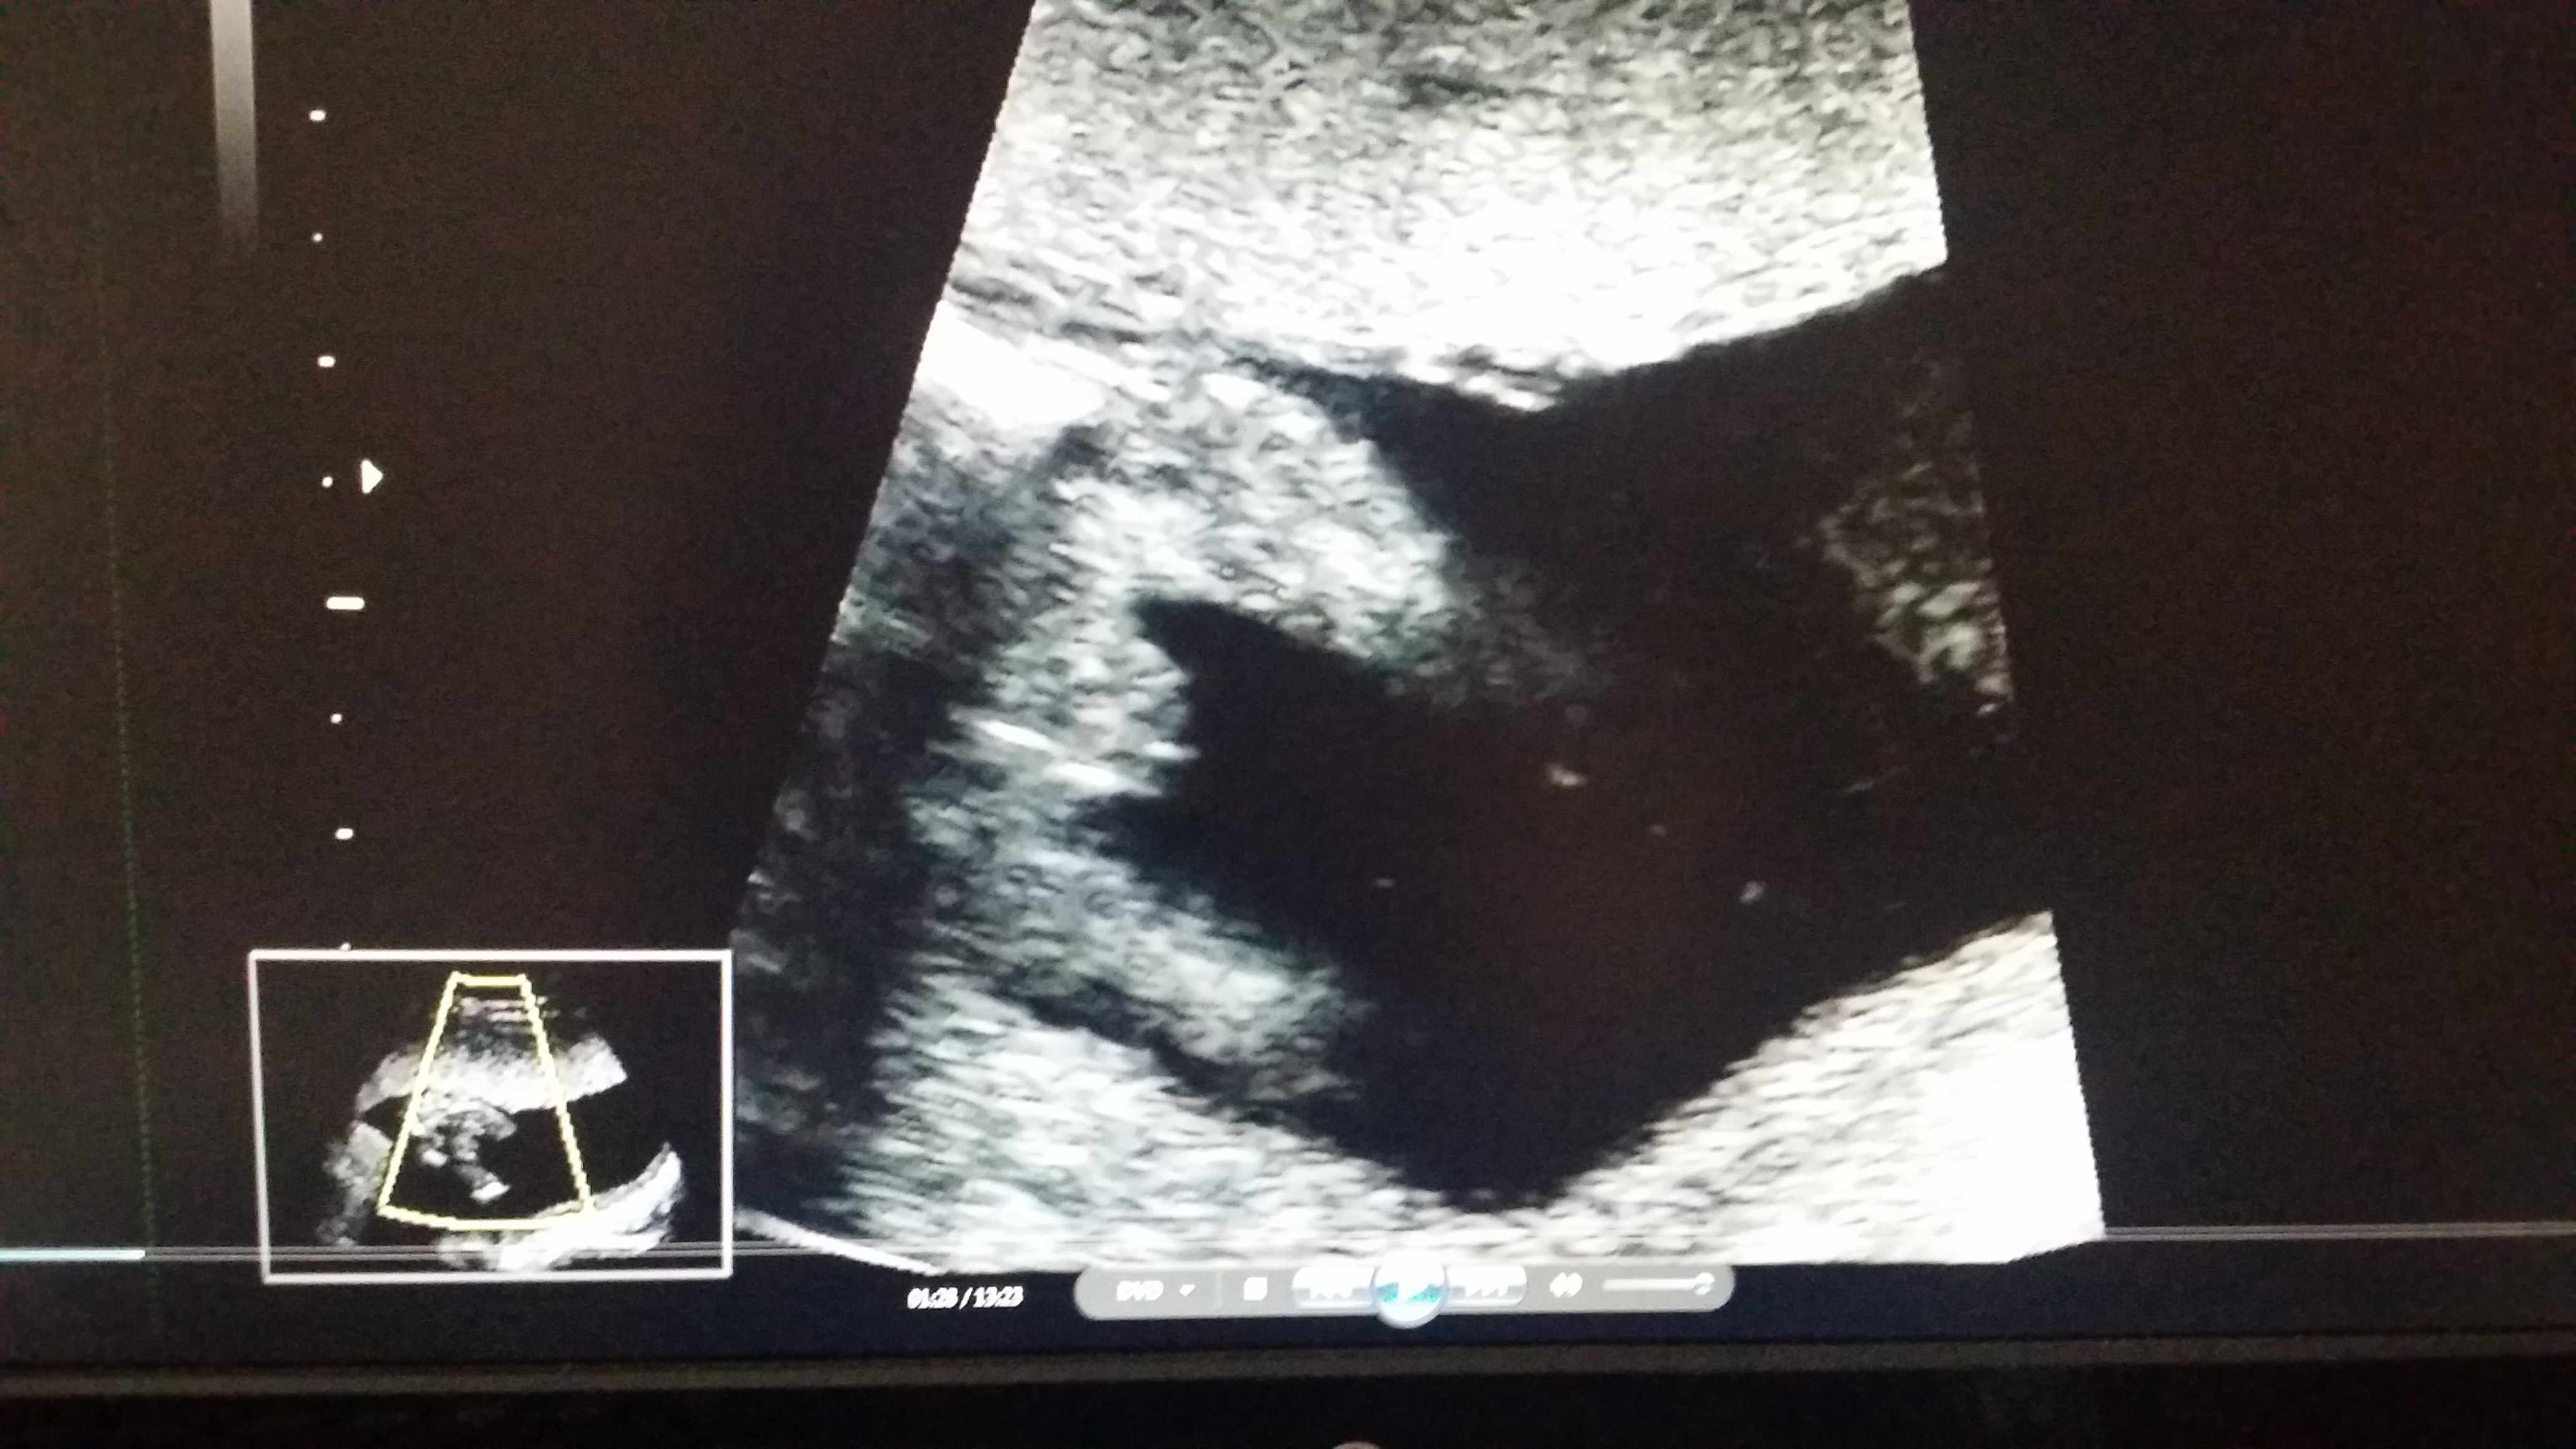

Attachment 21058

2nd image shows boy parts. Congrats!